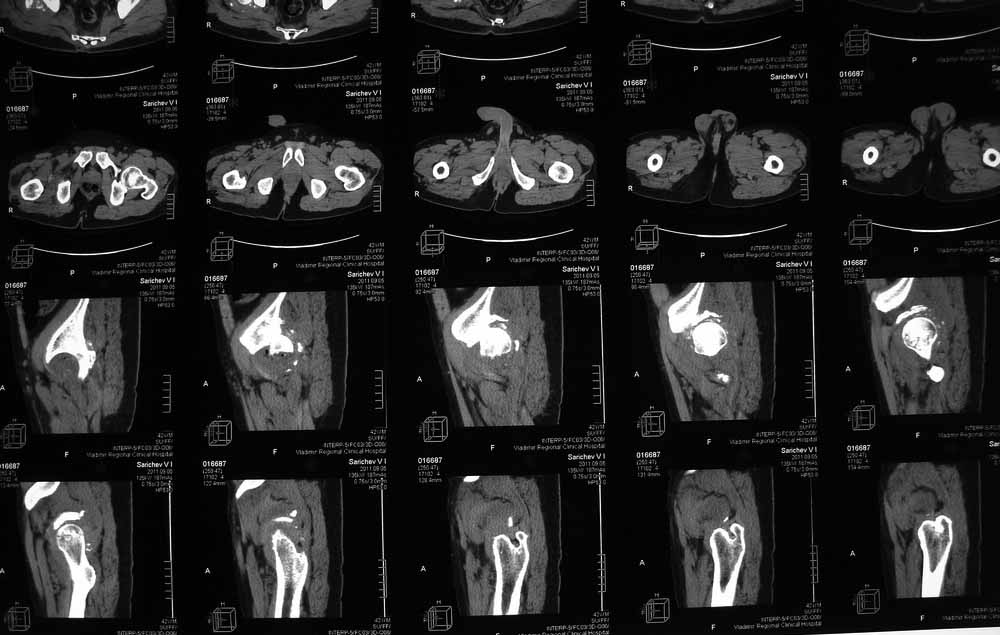

42 года, майор запаса. Травма от 20.06 - ДТП. Лечился в гражданском ЛПУ. Вывих бедра диагностирован только 4 недели спустя. "Тянулся", неоднократно - попытки закрытой репозиции. Попытка открытой репозиции - без результата. Потом опять пытались закрыто, сказали, что вправили, тянулся. После снятия ССВ - опять вывих. Поступил к нам. Сейчас - СРБ больше 10, в ОАК - воспаление. Местно - головка кзади и кверху, укорочение 7, голова подвижна. Отек, незначительная боль в в/3 бедра. Пассивно из наружной ротации выводится, активных движений в ноге нет. Рубец по наружной поверхности верхней трети бедра, без воспаления. Каким образом выполнялось открытое вправление - данных нет. Окончательно снят с вытяжения 2 недели назад.

Вот еще сканы.

В этой ситуации предпочел бы эндопротез, шансы на жизнеспособность головки в таком сроке вывиха исчезающе малы, попытка синтезировать задний край в этих же сроках (ретракция мышц, рубцы) скорее всего приведут к его девитализации с последующим аваскулярным некрозом. Выбор вертлужного компонента проще планировать после 3D, скорее всего можно будет обойтись стандартными предложением, возможно, с котилопластикой.